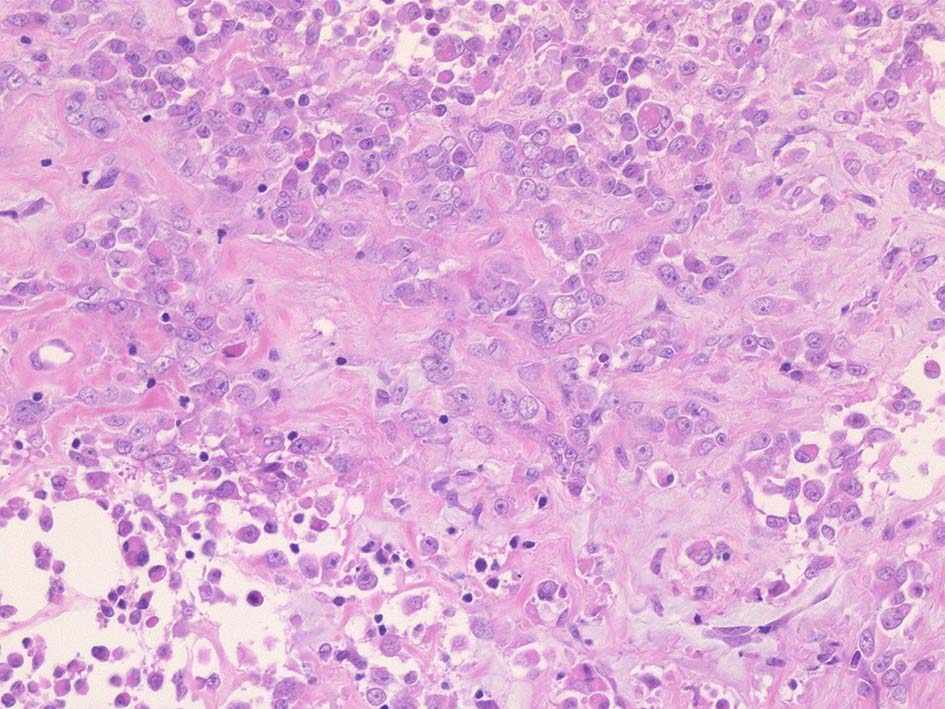

壁側胸膜腫瘤切除標本 病理組織所見

部分的に細胞接着性が低く疎な組織像を呈する.

① rhabdoid cellsが密に増殖する組織像. 核は類円形vesicularで, 中心性の大型核小体を1個もつ. 細胞質は好酸性.

球状の封入体様にみえる構造が出現し, 核偏在や核を圧排し, 三日月/半月状の核がみられている. mitosisが散在. 形質細胞が少数混在して認められる.

② 少量の線維性組織を間質に類円形/多稜形のvesicularな核と好酸性, 淡明な細胞質をもつ類上皮様の中~大型の細胞が集簇, 増殖している.mitosisが多い. 辺縁にはrhabdoid cellsのchohesiveな増殖が認められる.

③ 間質の線維組織が多く, 硝子化やmyxomatous changeが認められる. 二核の大型巨細胞が散在している. 細胞は比較的一様なサイズ形態で, 多型は高度ではない印象.